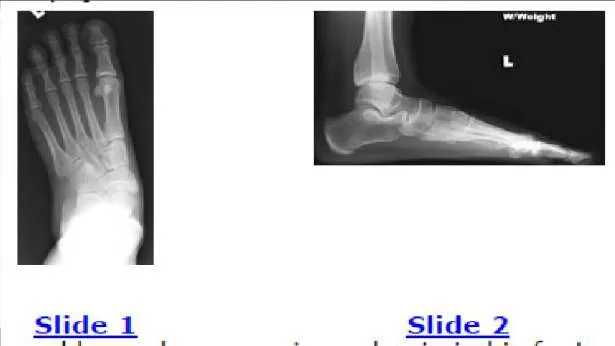

Question 10:

A 61-year-old woman presents for treatment of a painful ankle. She reports that 4 years ago, she sustained a fracture of her ankle that was treated with cast immobilization. She has experienced progressively worsening pain over the past 2 years. On examination, she has good range of motion of the ankle with crepitus and pain. Radiographs are presented (Slide 1 and Slide 2). All of the following are acceptable forms of surgical correction except:

Correct Answer: Ankle arthroscopy

Explanation:

Each of the alternatives presented is reasonable except for ankle arthroscopy because it has a limited role in the management of posttraumatic arthritis of the ankle. In this patient, there is a possibility to salvage the ankle before arthrodesis or joint replacement with an osteotomy of the tibia and or the fibula. Both have a definite role in management of ankle deformity and arthritis. A closing wedge osteotomy of the tibia was performed in this patient, and she remains asymptomatic 4 years later (Slide 3 and Slide 4).